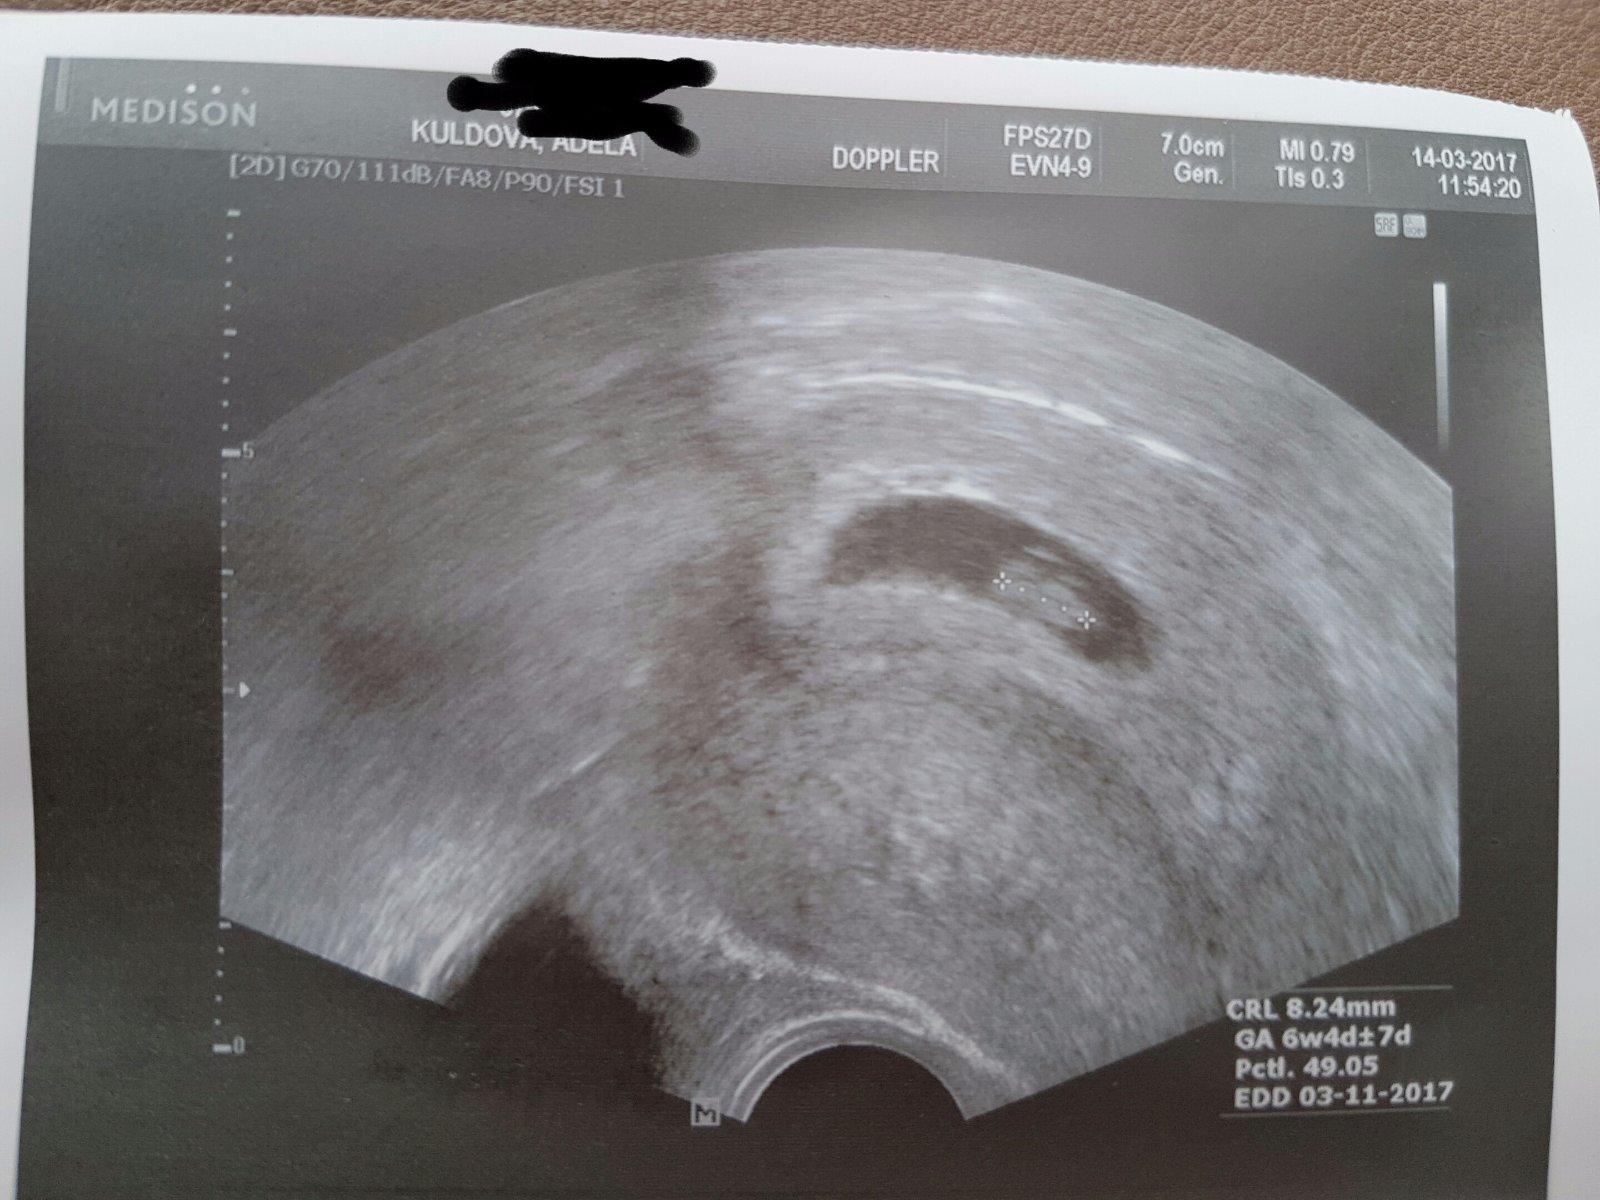

@jasmine2258 jsem ti v patach, 6+3 🙂 taky krasně bije, ta cevička 🙂))))

@8karolina4

Taky krásná bublinka 😍